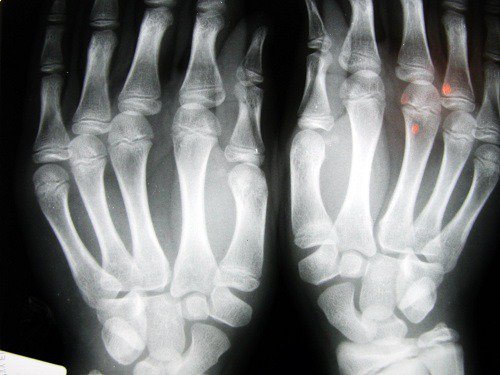

2. Grotere kans op artrose

Onderzoek uitgevoerd aan de Universiteit van Nottingham (Verenigd Koninkrijk) toont aan dat mensen die gemiddeld een kortere wijsvinger hebben, vaak ook een grotere kans lijken te hebben op het ontwikkelen van aandoeningen als artrose.

Dit is in verband gebracht met een tekort aan oestrogeen maar ook aan weinig lichamelijke beweging. Hier hebben vooral vrouwen last van.